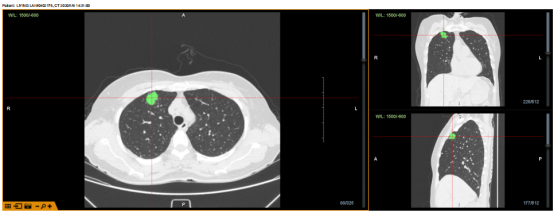

病例1:病灶位于右上叶前段,病灶大小约2cm,POE点位于RB3亚亚段,隧道长度36mm,使用FlexNeedle针穿刺,球囊扩张,再送入鞘管,于X光及超声下确认抵达病灶约耗时20份。

病例1

X光与超声确认抵达病灶